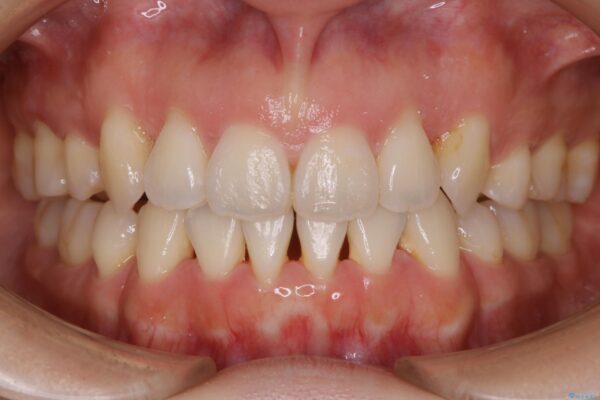

来院動機

前歯のガタつき、噛み合わせの不調を改善したいとご来院されました。

オープンバイト